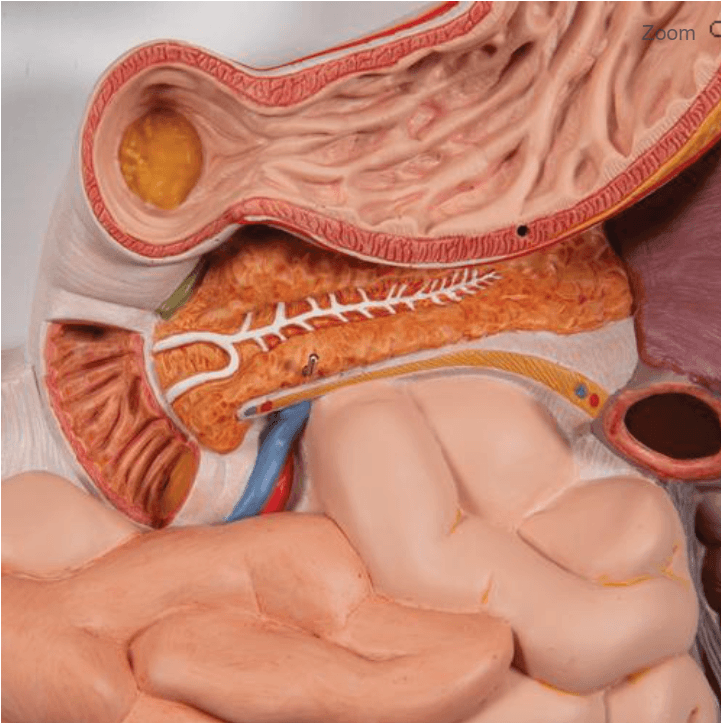

Dešinėje modelio pusėje esantis kepenų ir skrandžio segmentas išimamas, todėl galima apžiūrėti vidaus organų tarpusavio santykį iš kelių kampų. Tokia konstrukcija leidžia lengviau paaiškinti virškinimo proceso eigą ir vidaus organų funkcijas.

- Tiksli žmogaus virškinimo sistemos anatomija nuo burnos iki tiesiosios žarnos

- Nuimamos dalys: kepenys su skrandžio dalimi, atidaromas skrandis

- Matomi vidaus organų paviršiai ir struktūros